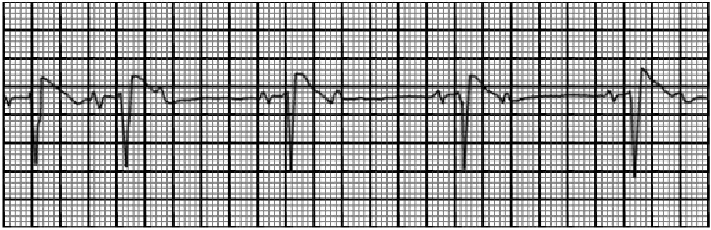

You are incorrect - the best interpretation of the rhythm strip in our patient is type I second degree A-V block.

This rhythm strip shows sinus rhythm with blocked premature atrial complexes. The characteristic feature demonstrated here include premature P waves which may have a different morphology from the sinus P waves and are not followed by a QRS complex. The PR interval of the sinus beats remains constant. The early atrial complex reaches the A-V junction before repolarization has been completed and is not conducted.